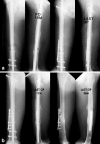

We reviewed 15 patients with femoral non-union after interlocking intramedullary nailing treated with plate augmentation and bone grafting with the nail in situ. The mean time from primary nailing to plate augmentation and bone grafting was 10 months. At the time of presentation, the patients had undergone an average of 1.6 operations from the time of their original injury. To achieve stability of the fracture, we applied an AO plate on the lateral aspect of the femur. The retained nail maintained alignment of the fracture, and plating did not require an extensive surgical approach. In all patients, there was visible motion at the fracture site; however, the motion disappeared after plate augmentation. All patients achieved radiological solid union at an average of 7.2 months.